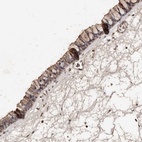

Immunohistochemical staining of human nasopharynx shows moderate membranous positivity in ciliated cells.